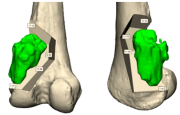

| 13:59, 14 באוגוסט 2023 | שתל פיבולה1.png (קובץ) |  |

252 קילו־בייטים | Motyk | 1 | |